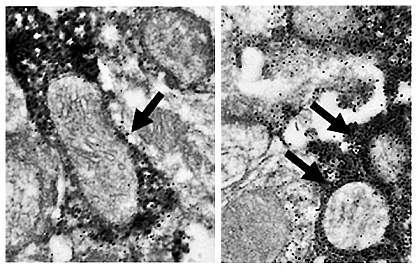

The underlying causes of neuron death in Parkinson’s disease aren’t well understood. Recent studies have linked dysfunctional mitochondria as one of the pathways causing neuron death. These organelles convert compounds derived from food into the molecules that cells use for energy. Studies suggest that proteins involved in the dynamics of these organelles—how they divide (fission), combine (fusion), and move—may play a role in Parkinson’s disease.

The scientists tested the effects of blocking or promoting mitochondrial fission by using genetic engineering techniques. To block fission, they used a mutant version of dynamin-related protein 1 (Drp1), a protein involved in fission. To promote fission, they boosted levels of Fission-1 (Fis1), which helps bring Drp1 to mitochondria.

The Drp1 mutant restored dopamine release and protected neurons in both mouse models, while Fis1 did not. To confirm that blocking mitochondrial fission was causing these benefits, the researchers tested a small molecule called Mitochondrial Division Inhibitor-1 (Mdivi-1). Mdivi-1 is a Drp1 inhibitor that’s been shown to block mitochondrial fission. They found that Mdivi-1 also restored dopamine release and protected neurons in the mice.